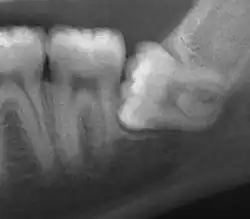

| Impacted wisdom tooth with a horizontal orientation | |

An ectopic tooth, also known as an impacted tooth, is a tooth that develops in an abnormal position (ectopia) and fails to erupt into its normal location in the oral cavity.[1] [2] Ectopic teeth can cause a variety of symptoms, such as pain, swelling, and infection, and they can lead to more serious complications if left untreated.

Ectopic teeth may commonly occur within the dentate region of the jaws. Other common sites for ectopic teeth include the maxillary sinus, the nasal cavity, the mandibular condyle, and the palate.[3] The cause of ectopic teeth is not always clear, but it may be related to genetic factors or developmental abnormalities.[4]

Diagnosis of ectopic teeth typically involves a comprehensive dental examination, including X-rays and other imaging tests. Treatment options for ectopic teeth depend on the location and severity of the condition, as well as the age and overall health of the patient. In some cases, observation and monitoring may be sufficient, while in other cases, surgical intervention may be necessary to remove the ectopic tooth and prevent further complications.[5]